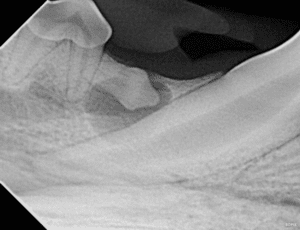

In this dog’s mouth, the right mandibular first premolar is absent.

A dentigerous cyst involving the right mandibular first molar.

Dentigerous cysts are fluid-filled sacs that can form around the crown of an impacted tooth. They are typically non-painful but can grow quite large and cause damage to the surrounding bone. It is impossible to predict which impacted teeth will develop dentigerous cysts or when it’ll happen, so the best thing to do is to extract the tooth before it happens. Dentigerous cysts can develop from any tooth in any dog, but are most common in the mandibular first premolars of brachycephalic (squish-faced) dogs.